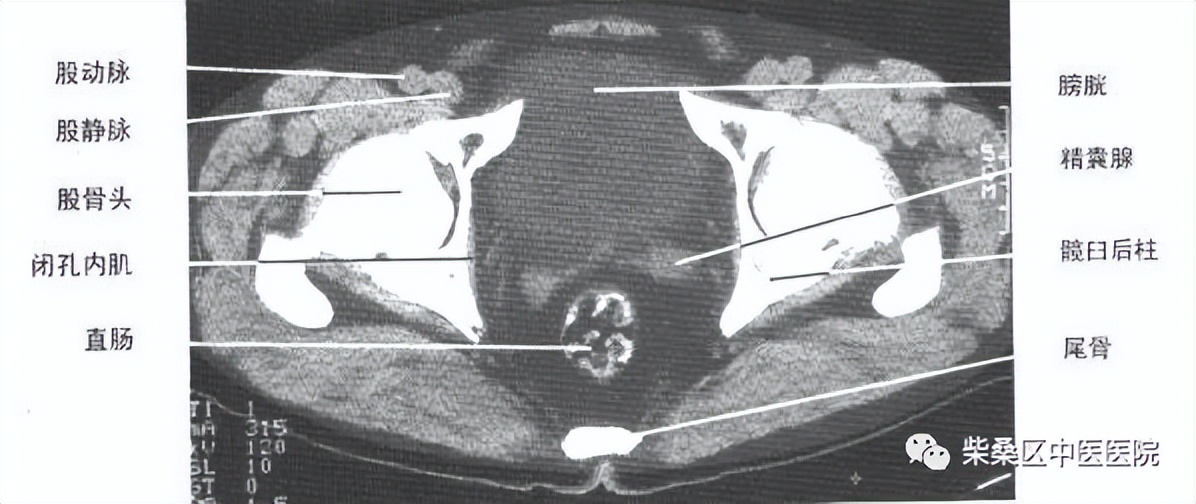

男性盆腔CT解剖结构

正常膀胱充盈可见水样密度影,还可以看见膀胱壁薄厚,正常充盈时,膀胱壁约5mm。例如膀胱有肿瘤、结石以及膀胱憩室等疾病时都需要在膀胱充盈状态时才会显示。另外在女性盆腔CT的检查中,充盈饱满的膀胱可以与子宫附件囊肿进行有效区分。